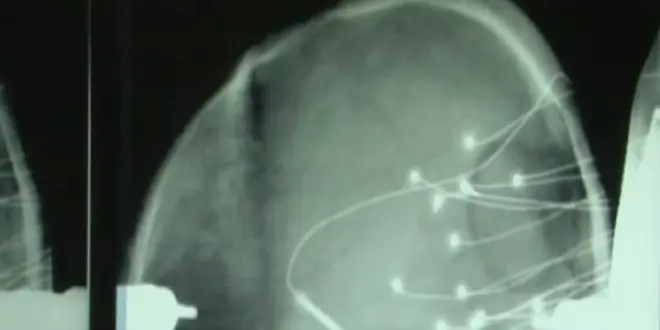

A Lyon une équipe de l'Inserm a essayé de comprendre les mécanismes de la lecture. Les chercheurs ont profité de la phase de repérage chez les patients opérés de l'épilepsie. Pendant une semaine, les malades ont des électrodes insérées directement dans le cerveau. Cela permet de localiser les zones responsables de l'épilepsie.

Pendant cette période, l'équipe du Centre de recherche en neurosciences, dirigé par Jean-Philippe Lachaux, a décidé de réaliser une expérience. L'idée était de faire lire un conte de fées à ces patients et d'observer l'activité électrique produite par les neurones dans le cerveau.